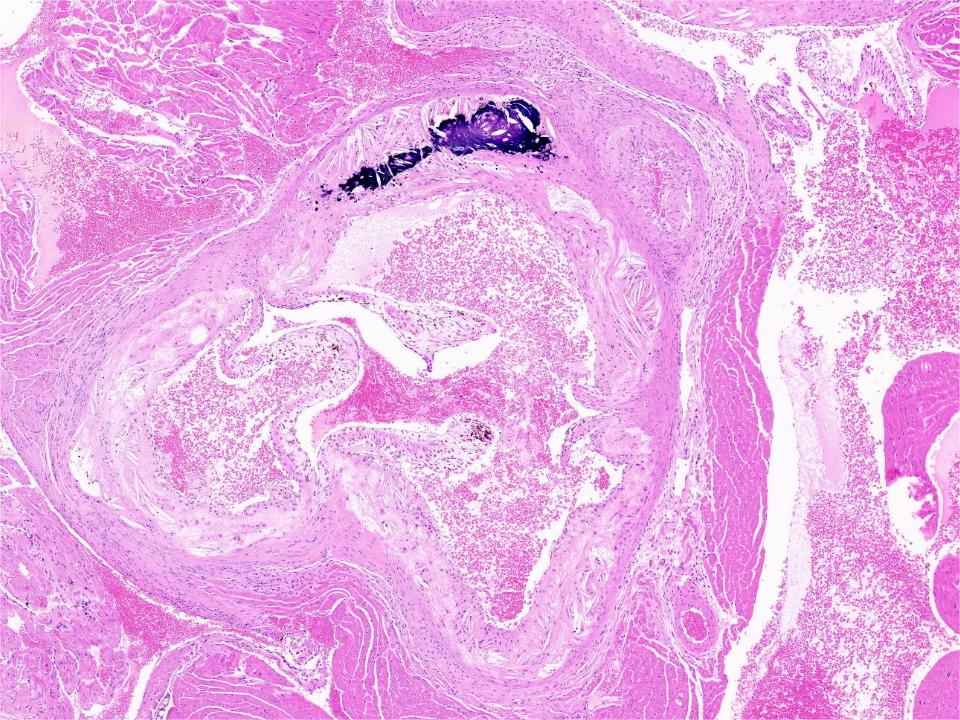

动脉粥样硬化动物模型